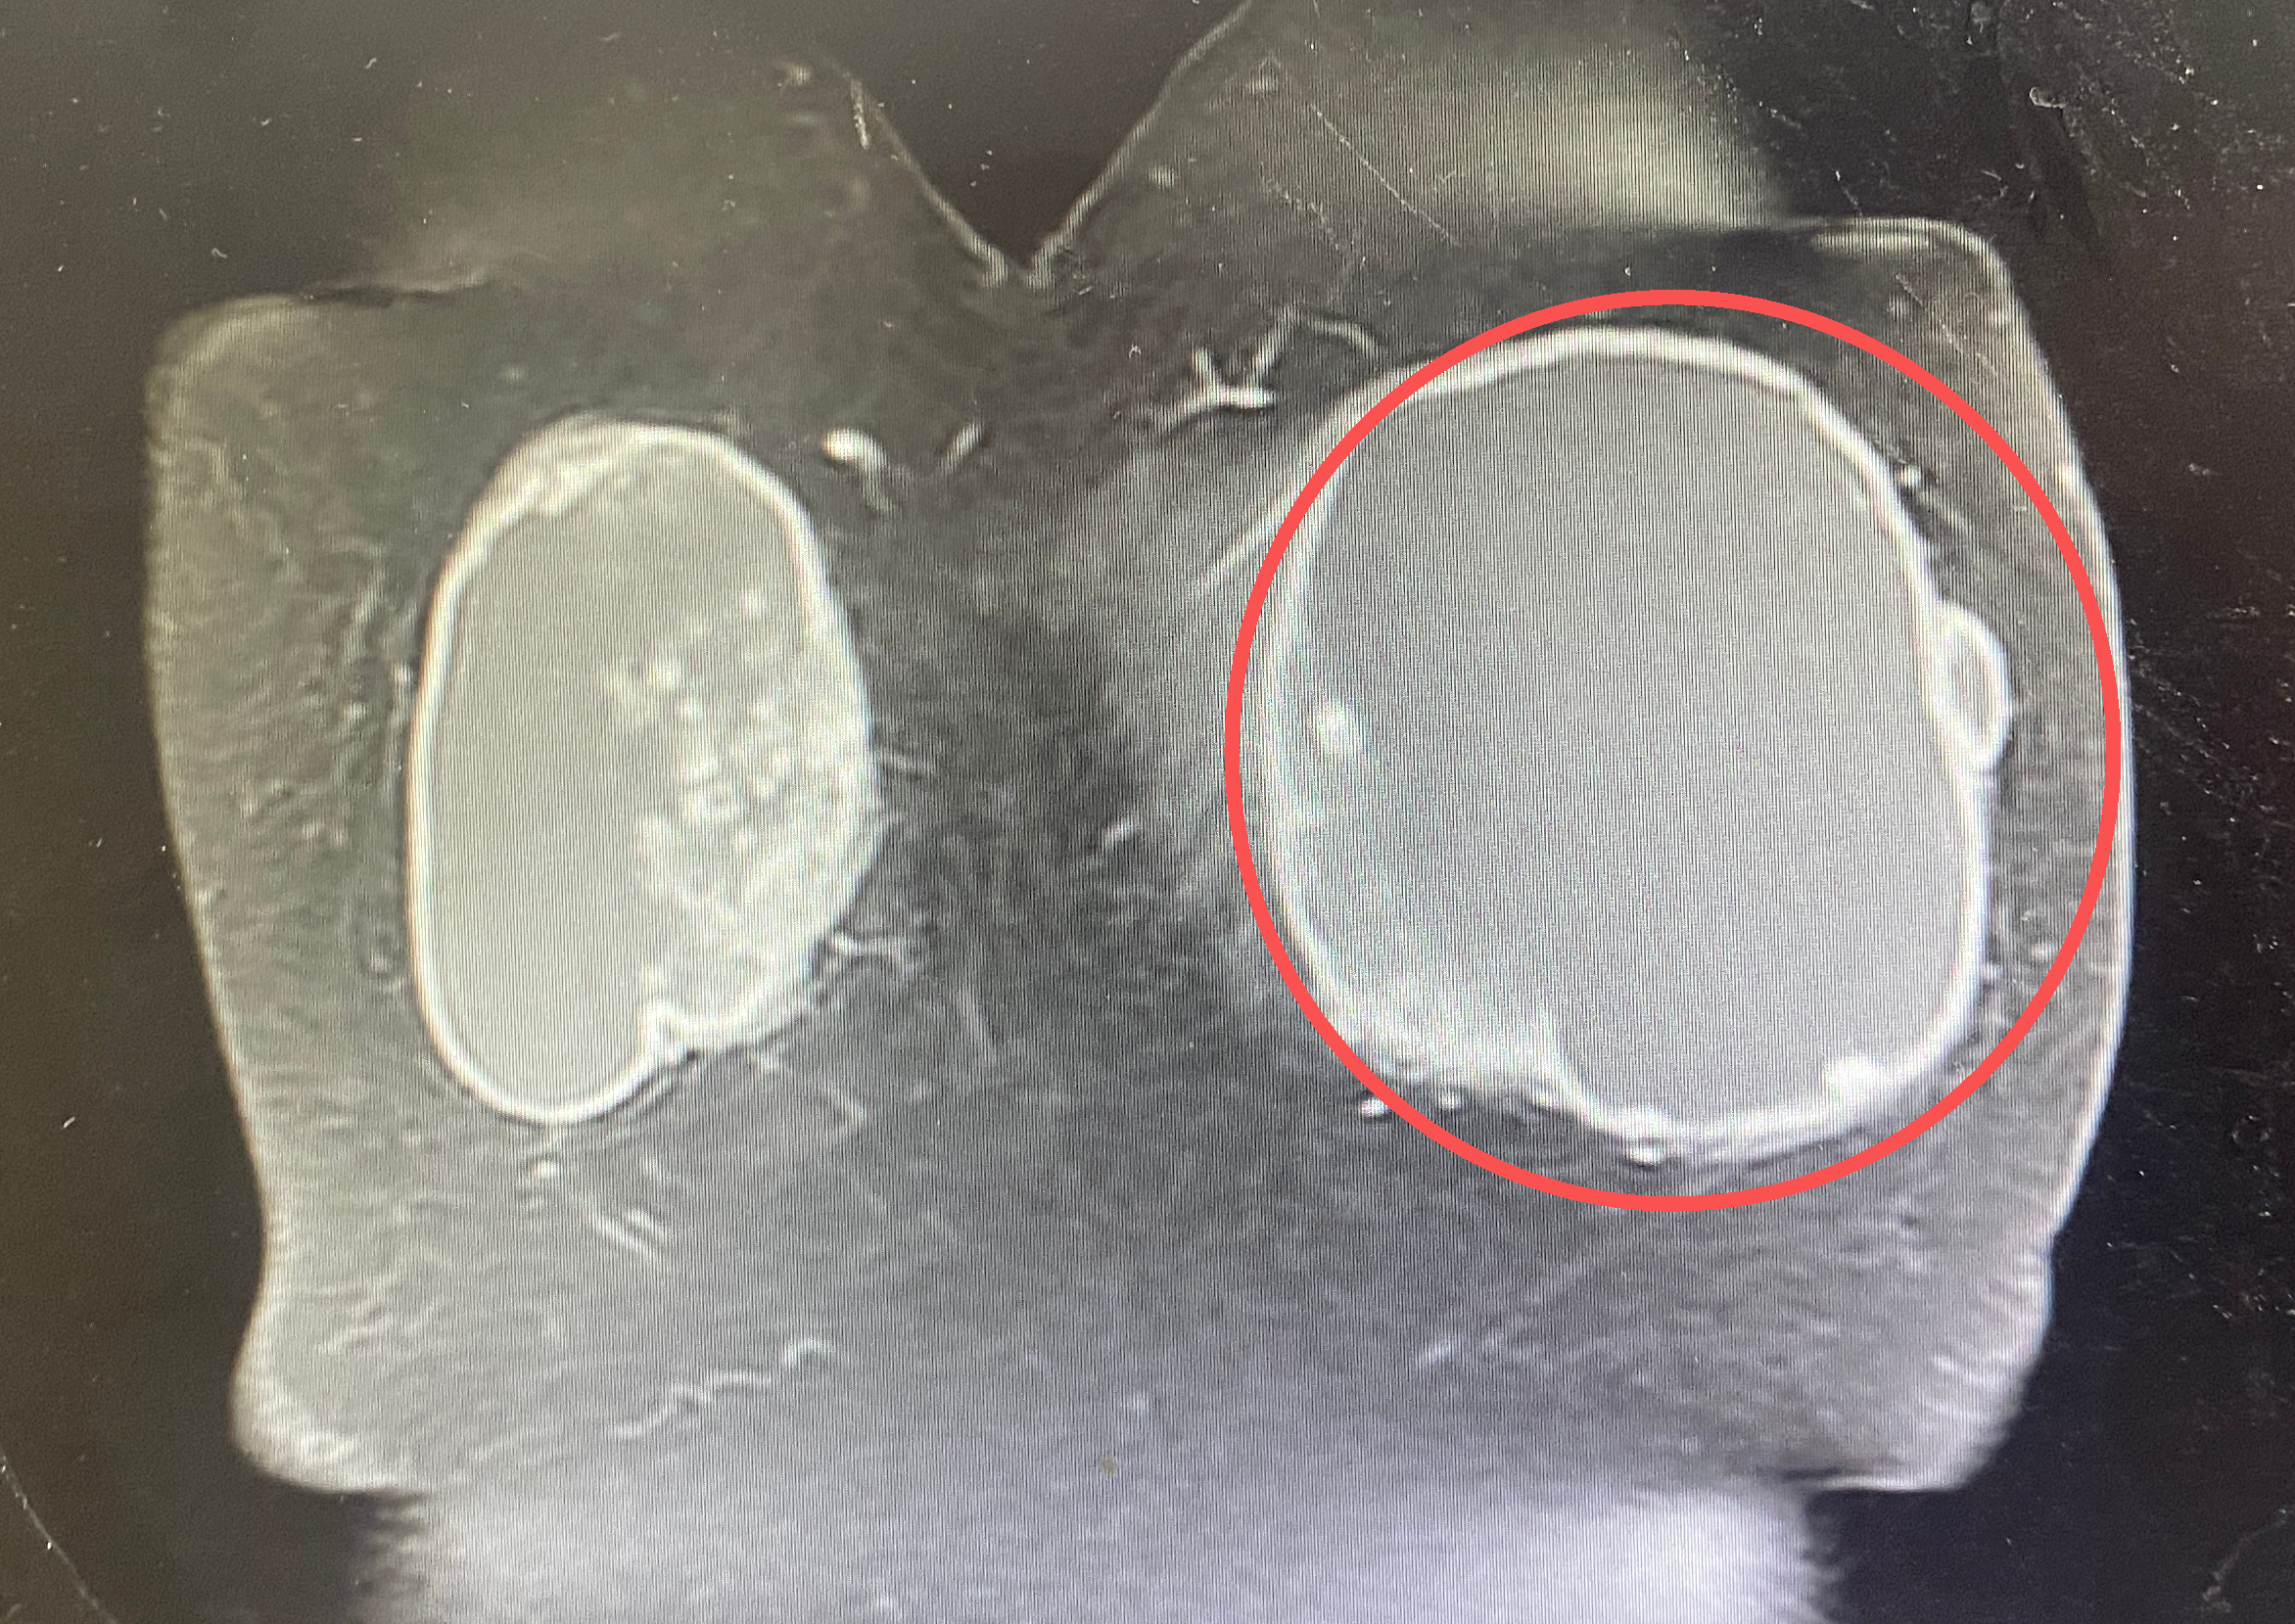

当乳房包块从鹌鹑蛋大小悄然长成足球般的惊人尺寸,多年前植入的美容假体,竟与罕见的恶性肿瘤在体内意外并存……近日,昆明同仁医院普外科专家团队为一名腺样囊性癌患者实施了乳腺癌改良根治术,不仅清除了巨大病灶,更显著改善了患者的术后生活质量。

几个月前,刘阿姨(化名)在洗澡时摸到左侧乳房有个鹌鹑蛋大小的包块,还伴有轻微疼痛,本以为是普通增生,便没有及时就医,仅偶尔用热毛巾热敷来缓解不适。可这个看似不起眼的包块,却在短短半年内“疯狂生长”,体积从最初的小巧模样迅速“膨胀”到足球大小,双侧乳房也变得严重不对称,穿衣服时的尴尬和活动时的牵拉痛,也让她终于意识到问题的严重性。

更为棘手的是,刘阿姨多年前曾接受双侧乳腺奥美定注射,如今乳房异常“肿大”,令她忧心不已,在子女反复劝说下,她慕名来到昆明同仁医院普外科就诊。李萍医生初步触诊,便在其左侧乳房发现了一个直径约15厘米的巨大包块,情况堪忧,随后的影像检查显示,她多年前注射的双侧乳腺奥美定假体已出现性状异常,这些异常的假体同时也干扰。

影像判断。鉴于巨大包块的存在和极高的恶性风险,必须进一步检查明确诊断。

为尽快明确包块性质,普外科专家团队第一时间为刘阿姨安排了左侧乳房包块穿刺活检术。活检过程中,医生凭借丰富经验精准定位,最大程度减少创伤,后续经免疫组化检查,最终确诊其为腺样囊性癌。“腺样囊性癌虽恶性程度相对较低,但患者肿瘤体积较大且位于乳晕附近,加之此前有假体植入史,手术必须兼顾肿瘤根治、假体取出与功能保护。”李萍医生说。

由于假体植入时间久、质地异常且存在潜在渗漏,导致其与周围组织形成致密粘连,分离难度较大。凭借丰富的临床经验,李萍医生在精细操作下逐步松解粘连,随后依照乳腺癌根治标准,李萍医生完整切除了直径约15cm的肿块及周围足够的安全边界组织,并顺利将左侧乳腺假体完整取出,术中冰冻病理检查证实手术切缘为阴性。